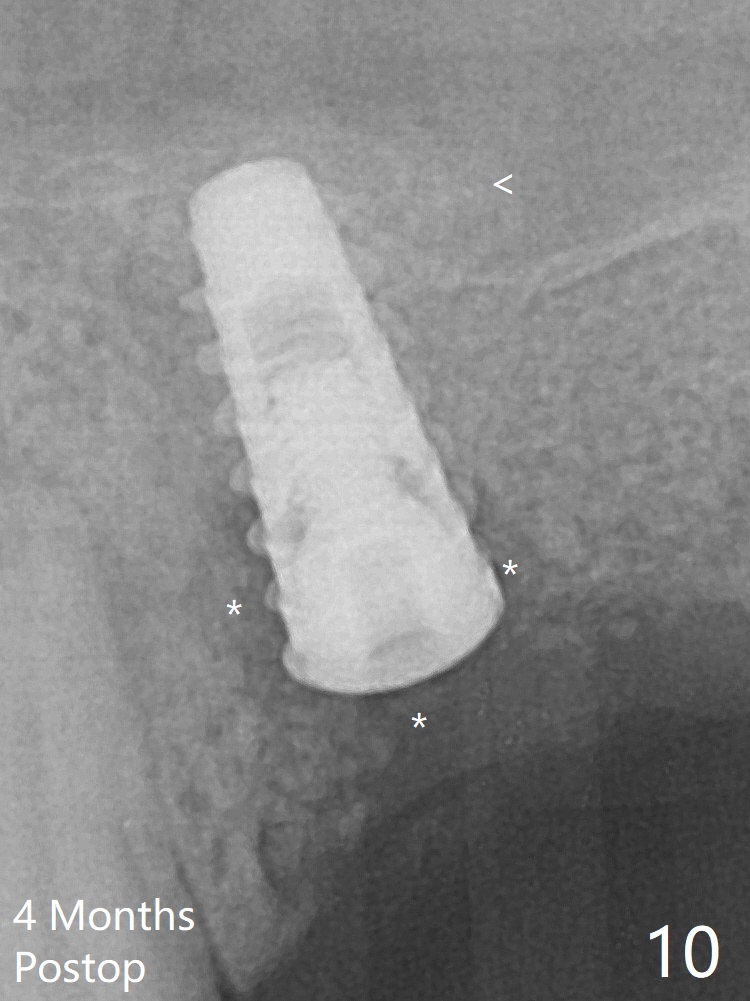

Five months post implant removal and bone graft, incision is made at #12. Osteotomy is being done with guide until 3.0x7.3 mm drill with 1 O-ring (palatal wall being thin), followed by 3.2x17-19 mm sinus round drills and 2.2x11.5 mm drill. After placement of 2 small loads of bone graft, a 4x9 mm dummy implant is inserted for sinus lift (Fig.1,2 *). By this time, the buccal plate is gone, while there is apparently the palatal periosteum. With more bone graft for sinus lift, a 4x9 mm final implant is placed with 30 Ncm (machine) and 4 mm subgingival (Fig.3,4 double arrows). Sticky bone (Fig.5,6 *) is applied around the coronal end of the implant and cover screw (S), followed by 2 pieces of PRF and 4-0 PGA suture. The sutures appear to have been dissolved and PRF membrane exposed 7 days postop (Fig.7,8 (smoker)). Four months postop, the wound heals except a small hole, which seems to be communicated with the underlying implant (Fig.9). The sinus lift remains (Fig.10 <), while bone loss appears to be present around the implant (Fig10,11 *). After placement of 5.5x4 mm healing abutment and before suturing, allograft is pushed into periimplant space (Fig.12, 13 *).